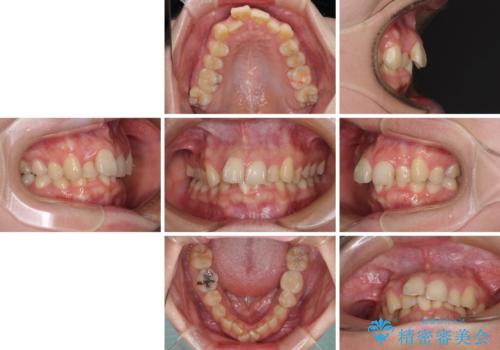

- 前歯のデコボコを気にして来院された患者様です。

上下の前歯にデコボコがあり、更にはディープバイトにより下顎前歯の大半が隠れている状態でした。

上顎左右第一小臼歯の2本を抜歯し、ワイヤー装置を使用して咬み合わせ高さを改善しながら、歯列を整えて行くこととしました。